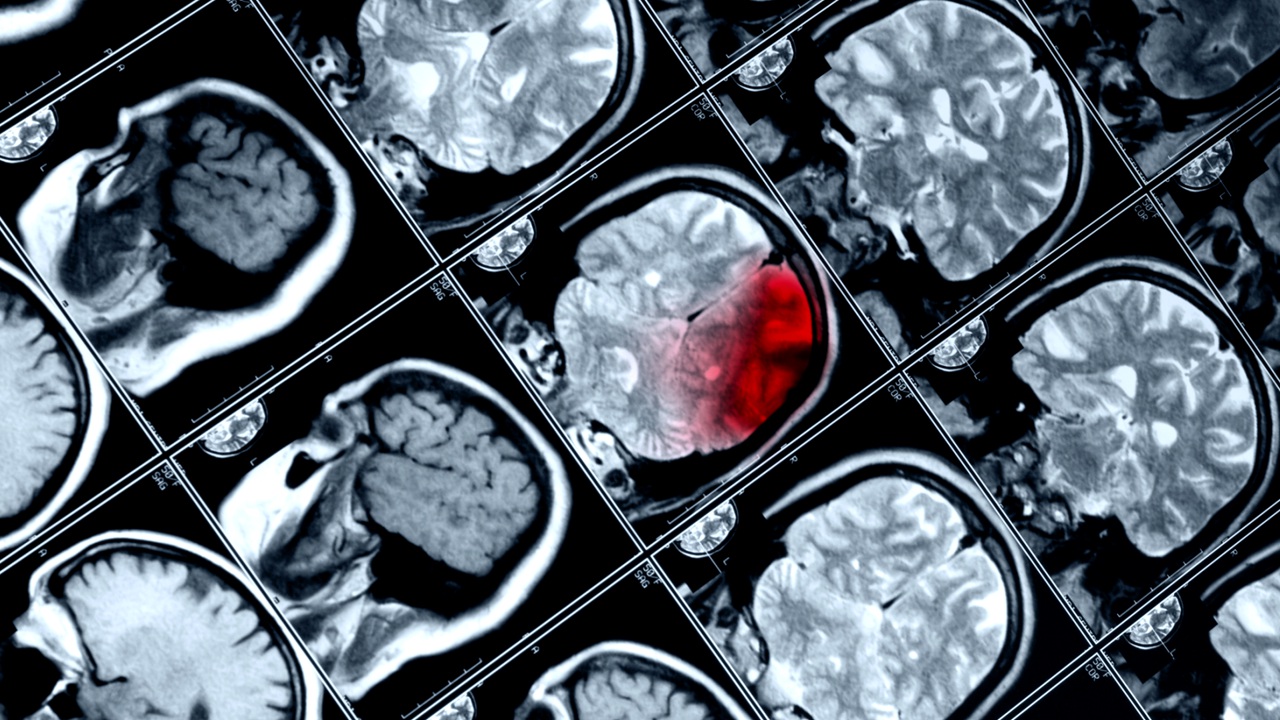

Όπως εξηγούν οι ερευνητές, όταν ο νωτιαίος μυελός ανθρώπων και ζώων υφίσταται μερική ρήξη, προκαλείται αρχικά παράλυση. Ύστερα όμως αρχίζει η αυτόματη, κοπιώδης πορεία προς την ανάκτηση της κινητικής λειτουργίας. Ωστόσο όταν η ρήξη του νωτιαίου μυελού είναι πλήρης, δεν είναι εφικτή η αυτόματη επούλωση της βλάβης και η παράλυση γίνεται μόνιμη.

Η ανάρρωση από τέτοιου είδους βλάβες απαιτεί να βρεθούν τρόποι αναγέννησης των «κομμένων» νευρικών ινών. Ύστερα πρέπει να βρεθεί τρόπος να ενεργοποιηθούν οι νέες νευρικές ίνες και μάλιστα με σωστό τρόπο για να υπάρξει επιτυχής αποκατάσταση της κίνησης.

Για να αντιμετωπίσουν το πρόβλημα, οι επιστήμονες πραγματοποίησαν εις βάθος αναλύσεις, που αποκάλυψαν τελικά ποιο είδος νευρώνων (νευρικών κυττάρων) είναι καθοριστικό στην αυτόματη επιδιόρθωση της μερικής ρήξης του νωτιαίου μυελού.

Ανακάλυψαν επίσης ότι αυτοί οι νευρώνες έπρεπε να ξανασυνδεθούν με συγκεκριμένους φυσικούς «στόχους» για να αποκατασταθεί η κινητική λειτουργία.